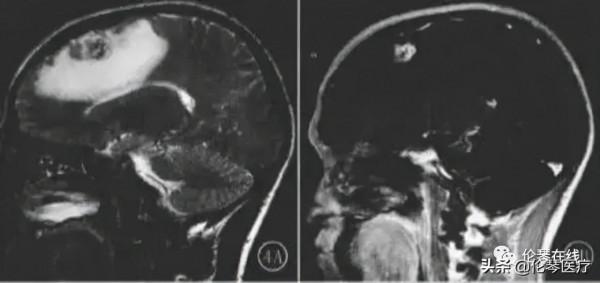

肺吸蟲腦病影像表現:病變常為幕上半球皮質和皮髓質交界區,累及單側大腦,多為單發,少數為多發。易受累腦葉為大腦中動脈分佈區,即頂、顳、枕葉,基底節區、丘腦較少受累,原因可能為肺吸蟲病沿頸內動脈向上爬行入腦,大腦中動脈是頸內動脈延續,且較粗大,所以沿大腦中動脈進入頂、顳、枕葉機會較大。兒童肺吸蟲腦病最常見影像學表現是腦出血,血腫位於大腦凸面皮質和皮髓質交界區,為肺吸蟲在腦內穿行遊走損傷腦組織導致血管破裂所致,因單一血腫與其他病因引起腦出血鑑別困難。

腦炎型肺吸蟲腦病MR特徵是隧道樣、環樣、結節樣強化,周圍伴有較廣泛水腫,其中“隧道徵”是其典型的特徵,MR表現為常約20 mm,寬約3 mm管狀結構,呈弧形或“V”形等,為肺吸蟲在腦組織穿行形成竇道軌跡。環形強化病理:蟲體停留破壞腦組織,內腦組織壞死液化,周圍為肉芽、纖維組織組成囊壁,多環形強化,病理為成蟲從一個囊內游出破壞腦組織,形成多個囊,囊間有隧道相通。

MR表現:簇狀分佈多個強化環、形成典型的“皂泡”徵,具有一定影像學特徵。強化結節病理為浸潤期肉芽組織增生和血管炎。結節狀、環狀、隧道樣強化MR表現反映肺吸蟲腦病組織破壞期、肉芽腫或囊腫期病理變化。3種類型可以單獨存在,也可以混合存在。後期病變消散,或遺留鈣化或腦萎縮改變,CT上可見點片、結節或環形鈣化。

MR表現為腦出血,增強不伴有結節、環狀強化灶

MR可見T2WI混雜訊號,周圍明顯水腫帶。增強可見多發相連環狀強化環

左頂葉多發環狀強化病灶聚集